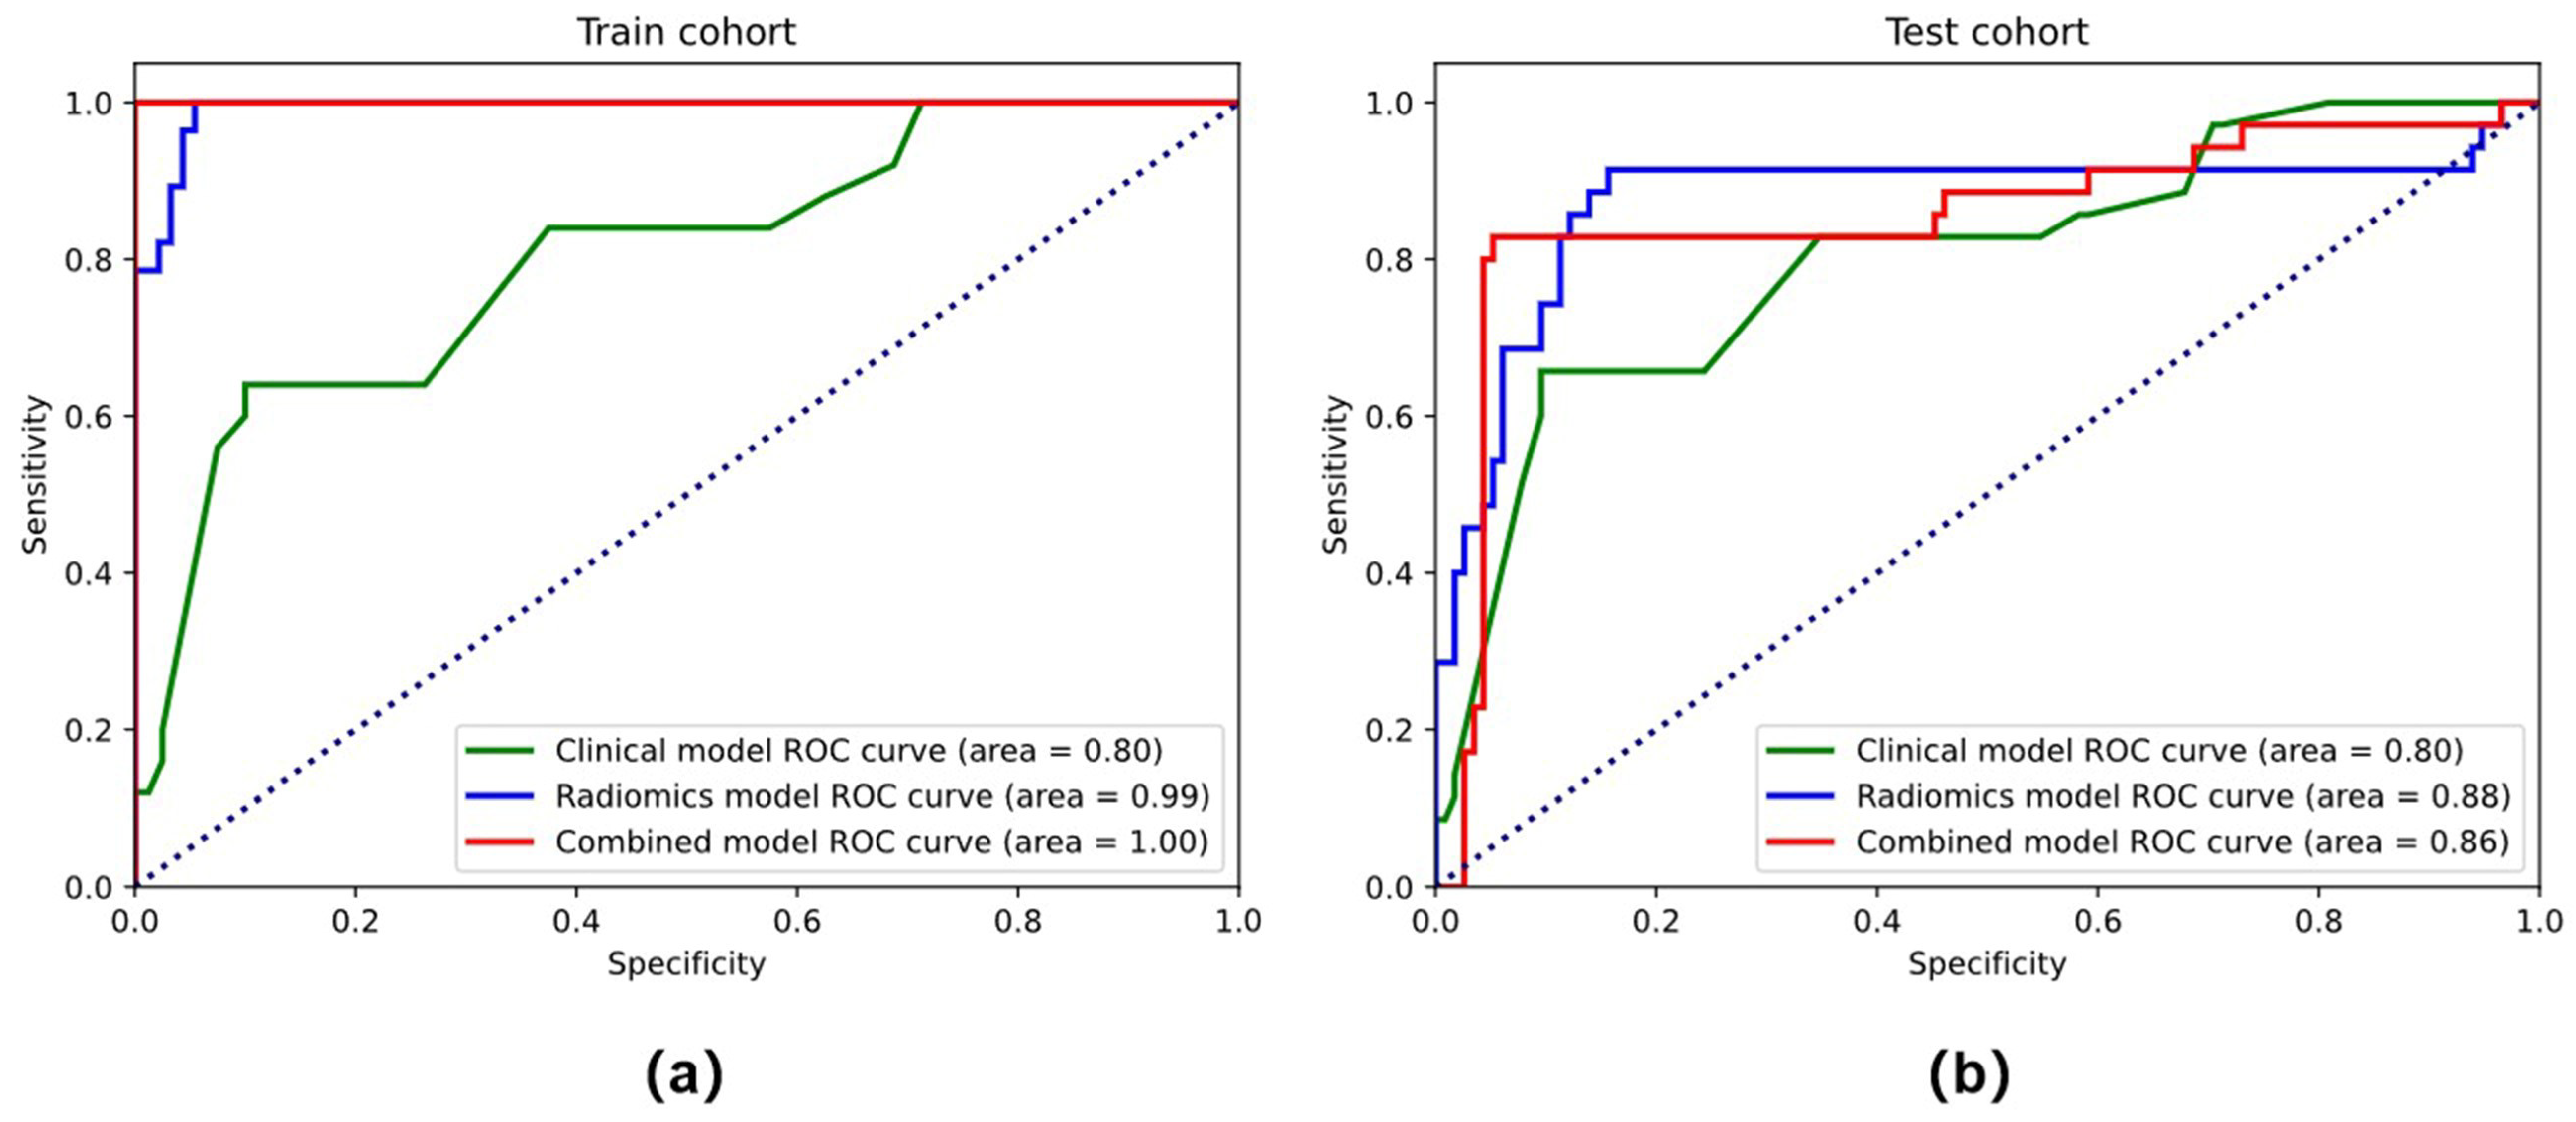

3.2. Feature Selection and Performance of the Clinical Model and Radiomics Model

3.3. Performance of the Combined Model and the Radiomics Nomogram

| Training Cohort | Testing Cohort | ||||||||

|---|---|---|---|---|---|---|---|---|---|

| AUC | ACC (%) | SEN (%) | SPE (%) | AUC | ACC (%) | SEN (%) | SPE (%) | ||

| Clinical | stage | 0.832 | 0.816 | 0.708 | 0.920 | 0.767 | 0.771 | 0.657 | 0.886 |

| pathology | 0.476 | 0.531 | 0.08 | 0.96 | 0.527 | 0.485 | 0.08 | 0.886 | |

| diameter | 0.712 | 0.714 | 0.75 | 0.68 | 0.728 | 0.729 | 0.771 | 0.685 | |

| Stage+pathology+diameter | 0.925 | 0.816 | 0.703 | 0.920 | 0.839 | 0.742 | 0.657 | 0.828 | |

| Radiomics model | 0.975 | 0.918 | 0.920 | 0.917 | 0.852 | 0.771 | 0.829 | 0.714 | |

| Combined model | 0.988 | 0.959 | 0.920 | 1.00 | 0.922 | 0.871 | 0.857 | 0.886 | |